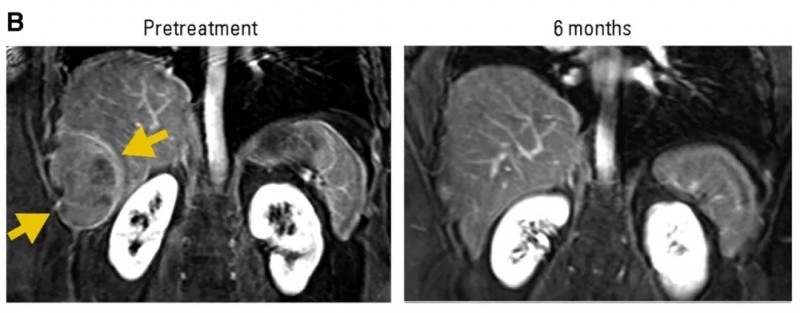

2、16号滑膜肉瘤患者:治疗后肝周胸壁滑膜肉瘤病灶消退,部分缓解(PR)持续8个月(详见下图B)。

▲图源“J Clin Oncol ”,版权归原作者所有,如无意中侵犯了知识产权,请联系我们删除